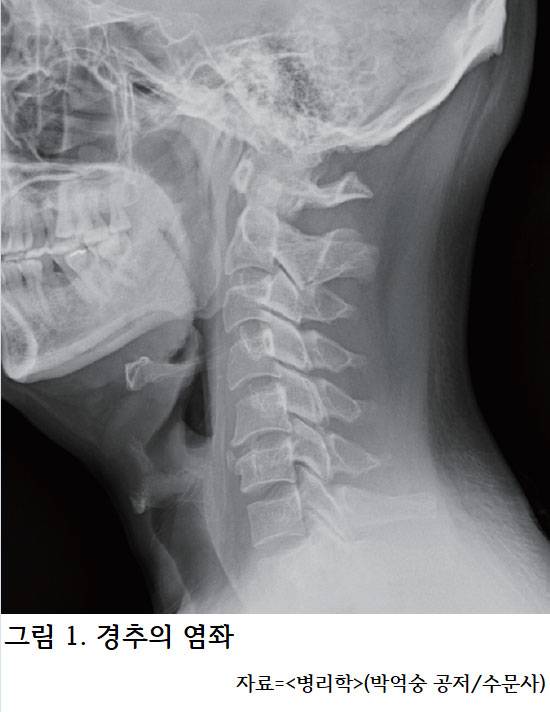

1. 교통사고 이후 병원에 도착하면 먼저 ‘x-ray’를 통해 골절과 경직 여부를 확인한다. (그림1) 심한 손상이 의심되면 입을 벌린 상태에서 찍는 ‘C-spine Odontoid (Open mouth)’를 촬영한다. 두 번째 경추의 한 부분인 치아돌기(Dens) 골절은 숨뇌를 누를 수 있기 때문이다. 통증이 심하면 ‘CT’를 통해 골절을 확진할 수 있다. 만약, 목과 양쪽 팔의 신경학적인 증상과 움직임 제한(LOM)이 있는 경우라면 ‘MRI’를 통해 척수신경 손상을 빨리 확인해야 한다. 이런 영상의 결과들을 바탕으로 대증치료와 수술 등 치료방법을 결정하게 된다. 교통사고 후 점점 심해지는 두통은 ‘뇌 CT(brain CT)’를 통해 뇌출혈이 있는지 꼭 확인해야 한다. 갑자기 발생하는 흉통, 복통도 진료가 필요하다.